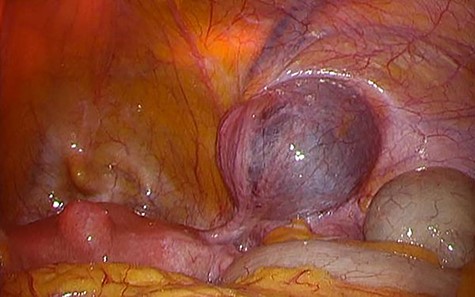

A 49-year-old woman presented with painless swelling in her right inguinal region. She had a history of caesarian section and no history of infantile inguinal hernia. Physical examination revealed a soft egg-shaped mass extending from the right inguinal region to the labia majora. The mass was seen as a protrusion when the patient was in the standing position, while it disappeared when the patient was in the lying position. Ultrasound revealed a well-defined hypo-echoic elongated mass that extended from the superficial inguinal canal, with no solid component (Fig. 1). Computed tomography (CT) showed that 55 × 34 × 95 mm oval fluid collection located at the right inguinal region near the cecum and retroperitoneum in the abdominal cavity (Fig. 2). Total colonoscopy found no mucosal abnormalities from the cecum to the rectum; however, a mass of tissue pushed the cecal wall from outside (Fig. 3). This hinted toward a large HCN, appendiceal tumor or retroperitoneal tumor; we decided to attempt a combined approach of conventional and laparoscopic methods for diagnosis and treatment of the swelling. We used three ports (12, 10 and 5 mm; Fig. 4) for our laparoscopic approach. We placed a 12 mm laparoscopic trocar into the umbilicus for CO2 insufflation of the pneumoperitoneum. Endoscopic intraperitoneal observation revealed that the mass was distant from the cecum and outside the peritoneum (Fig. 5). The tumor was large and was not completely observed using only an intra-abdominal approach. Therefore, we used a combined approach, which was the conventional method with a skin incision in the inguinal region in addition to the intra-abdominal method with laparoscopic approach. The tumor could be resected without any damage by observing from both directions (Fig. 6). We adopted the Direct Kugel Patch (ONFLEX®, C.R. Bard, Inc., USA) for the vulnerability of the posterior wall of the inguinal canal. Histopathological examination revealed that the mass contained single-layered mesothelial cells and no tumor or endometriosis. Based on imaging, histopathology and operative findings, we diagnosed her with an HCN. The patient recovered and did not have any postoperative complications, and she was discharged from hospital on postoperative day 6. She had no recurrence of hernia or hydrocele until 16 months postoperatively.

Successful laparoscopic techniques in the diagnosis or treatment of the HCN have been reported [2, 3]. Our endoscopic observations were particularly useful in revealing that the hydrocele has no communication with the peritoneal cavity and was mainly located in the extraperitoneal space [2]. The tumor was large and was not seen completely using only the intra-abdominal approach. Therefore, we used a combined approach, including the conventional method with skin incision in the inguinal region and the intra-abdominal method with a laparoscopic approach. The tumor was resected without any damage by observing from both inside and outside.